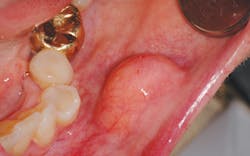

One such entity that is often perplexing to the clinician is the lipoma. (see Figure 1) It is one of the most common total body tumors, yet it is also a rare benign neoplasm not often found intraorally. In order of occurrence when found intraorally, these growths may occur on the buccal mucosa (because of the abundant fatty tissue), the tongue, the floor of the mouth, buccal sulcus, palate, lips, and gingiva (Kumaraswamy et al.2009). They have also been found in the oral pharyngeal area and may interfere with swallowing. This is another excellent reason to critically examine the tonsillar and pharyngeal areas since tonsillar cancer is a prime concern as well.

Lipomas are slow growing, painless, soft, smooth-surfaced, palpable masses, and are noted as having a yellow hue. They are unlike the fibroma, which does not normally present with a yellow-tinged surface and presents a more firm and flesh-toned appearance.